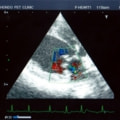

症例:【マルチーズMix 1歳齢 メス】

A:胸部レントゲン写真 正面像

B:胸部レントゲン写真 側面像

C:超音波画像 肺動脈領域の異常血流

D:左心系の拡張による二次的僧帽弁逆流

左側胸壁よりLevine 4/6の連続性心雑音が聴取された。胸部レントゲン検査において心拡大が認められ、超音波検査においても肺動脈領域に連続的な異常血流が観察された。大学病院を紹介受診され、手術が行われた。現在はACE阻害薬のみの内服で補助的治療を行っている。